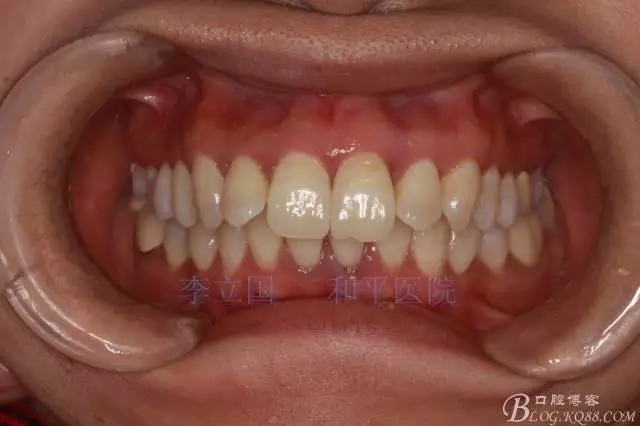

患者主訴前突。

1.患者上前牙直立,面型前突,典型的嘴凸牙不吐,關(guān)鍵是前牙轉(zhuǎn)矩控制,建議使用高轉(zhuǎn)矩托槽。

2.磨牙關(guān)系一側(cè)完全遠(yuǎn)中,一側(cè)遠(yuǎn)中尖対尖,采用兩個上4,一個下1的拔牙模式。